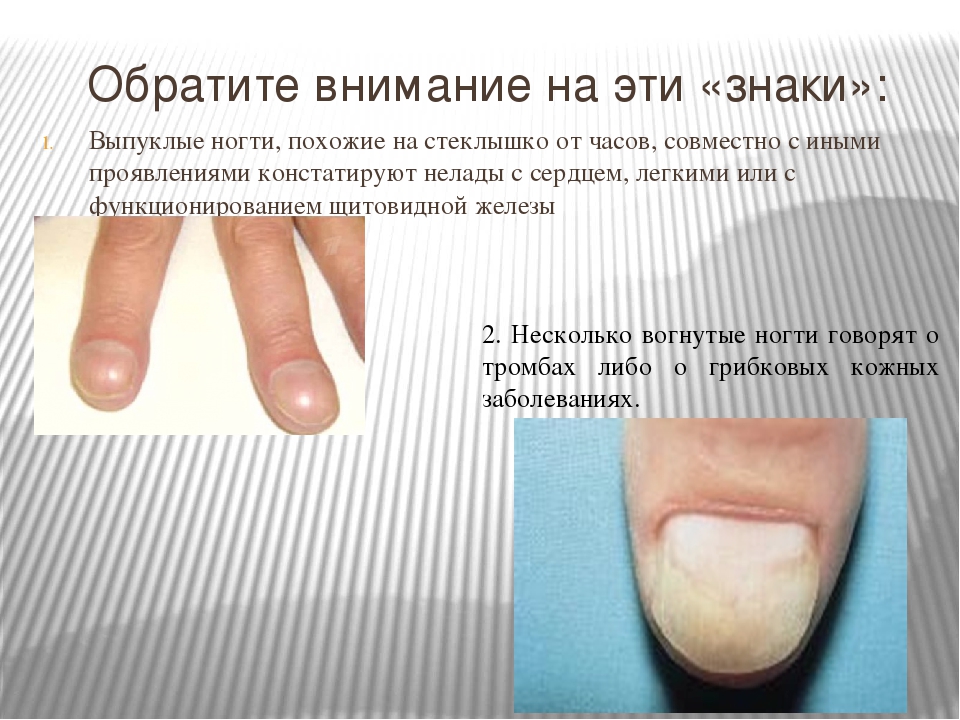

Грибковые заболевания ногтей: буклет с информацией